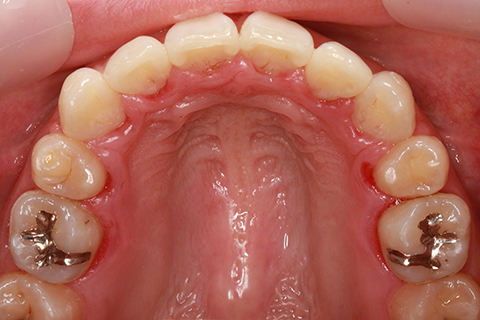

ハーフリンガル矯正3(上の歯のみ舌側矯正で治療)

治療前

治療中(開始直後)

治療中(開始半年後)

治療後

- 年齢・性別

- 25歳女性

- 治療期間

- 2年0ヶ月

- 抜歯

- 上下4番抜歯

- 治療費

- 110万円

- 治療内容

- 施術の副作用(リスク)

- 表側矯正と比較して、力学的な操作性が複雑なため、ボーイングエフェクトを起こしやすい。